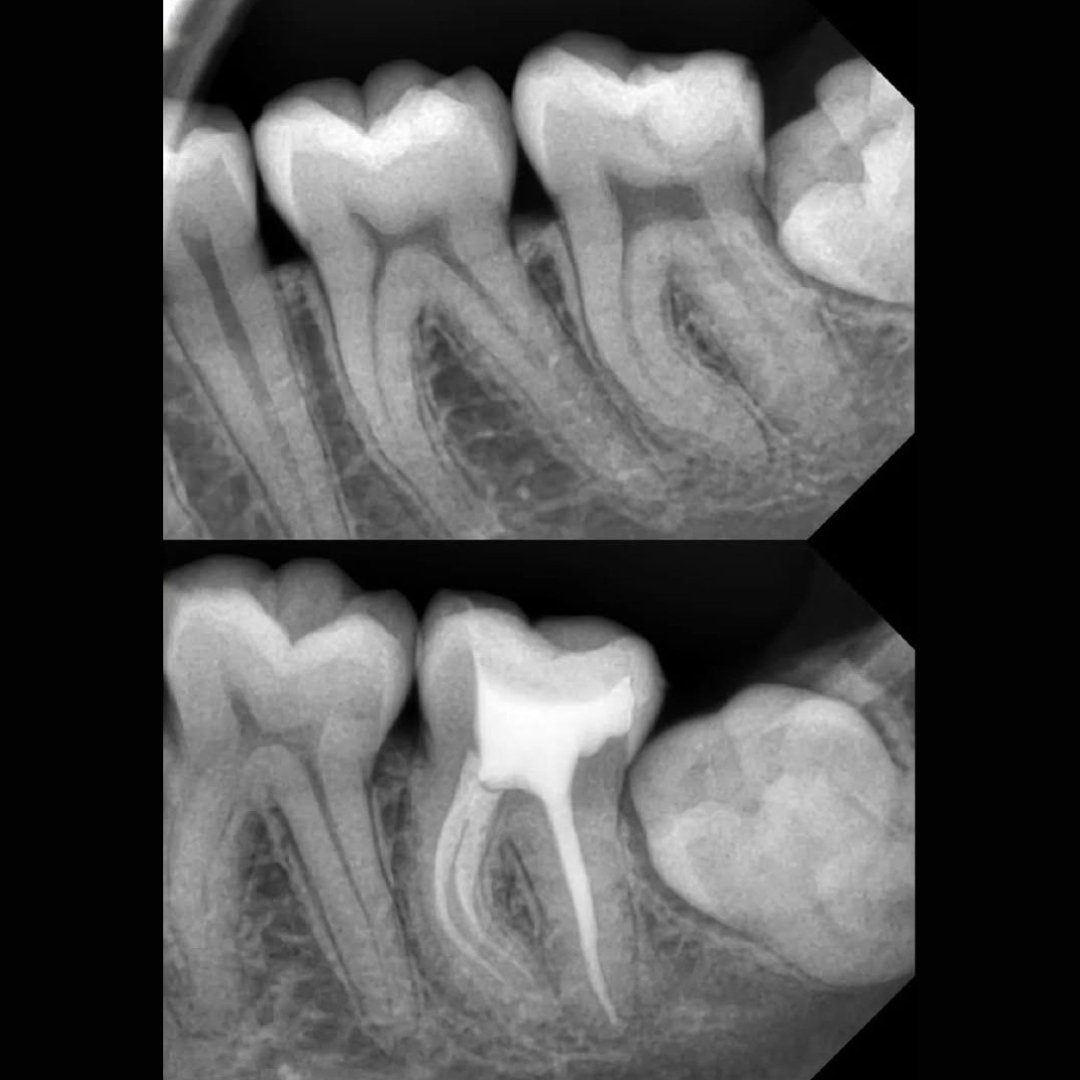

Before After Perawatan Saluran Akar (PSA) di Klinik Utama Pondok Gigi Jakarta

Transformasi nyata setelah perawatan saluran akar (PSA) di Klinik Utama Pondok Gigi Jakarta. Dari gigi rusak dan nyeri hingga kembali sehat dan berfungsi normal. Dikerjakan oleh dokter gigi profesional dengan teknik endodontik modern dan alat berteknologi tinggi untuk hasil maksimal.